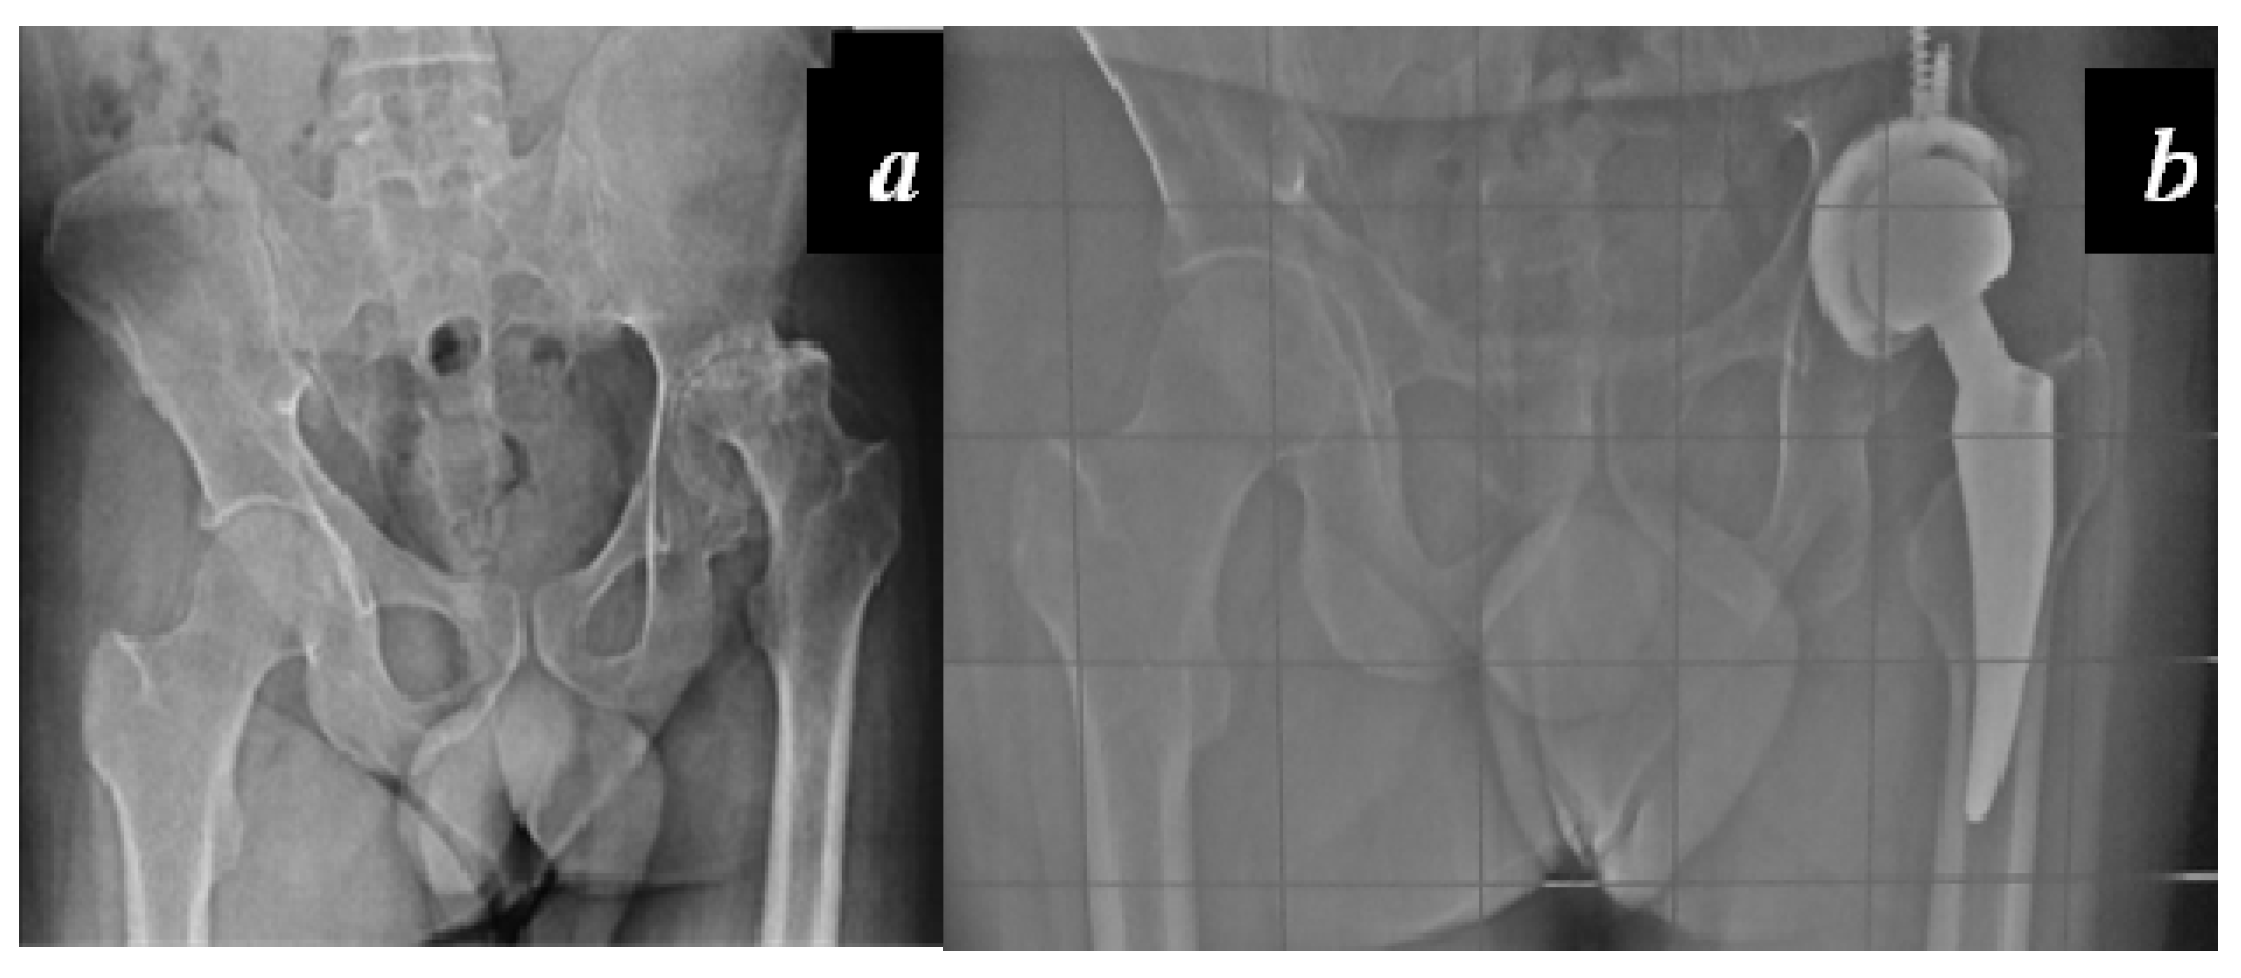

Carulli et al. reported a series of 23 haemophilic patients undergoing THA with modern cementless implants and COP couplings [1]. In 14 subjects, a standard stem was used, while in nine cases a modern short stem was adopted. No failures and no complications were recorded, with a survival rate of 100% at an 8.1-year follow-up (Figure 3 and Figure 4).

Figure 3. (a) Preoperative X-rays of the left hip of a 58-year-old patient affected by severe haemophilia A; (b) Radiographic aspect 6.5 years after surgery: Standard cementless tapered stem with ceramic-on-polyethylene (COP) coupling.